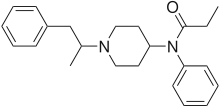

Anilidopiperidines